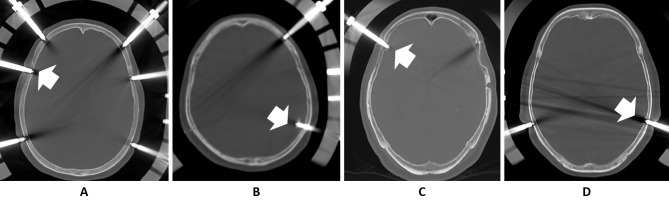

Introduction: A halo vest is an immobilization device widely used to stabilize the cervical spine. Pain and infection at the skull pin insertion site are common complications, but skull perforation is rare, and most published studies are case reports. This study aimed to identify risk factors for skull perforation by comparing patients who did and did not develop perforation.

Methods: Overall thickness and the thicknesses of the internal and external laminae of the skull at the skull pin insertion sites were measured on cranial computed tomography scans of 66 patients fitted with a halo vest. The results were compared between patients who did and did not develop perforation.

Results: Four patients developed perforations. All patients with perforation were older women, and their external and internal laminae were significantly thinner than those of patients who did not develop perforation.

Conclusions: The reported causes of skull pin perforation include infection around the pin, osteoporosis, and an enlarged frontal sinus. However, most patients with perforation in the present study were older women, and the cause was the thinning of the external and external laminae.